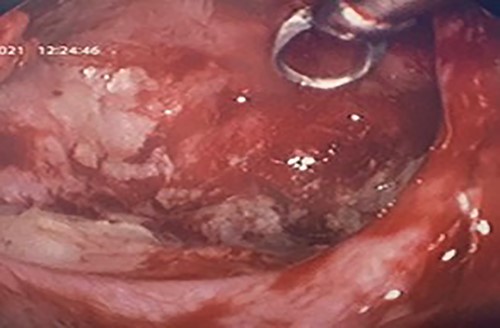

Flexible nasendoscopy offered little in terms of diagnostic benefit. An exam under anesthetic with a view to removing the ectopic tooth via endoscopic sinus surgery was warranted. Right middle turbinate trimming along with a right maxillary antrostomy was performed. The tooth was immediately identified at the antrum as depicted in Figs 4–6. The bony capsule of the tooth was entered and, on manipulation, a second ectopic tooth was identified (Fig. 7) both of which were removed en bloc. The cystic component within the maxillary sinus was marsupilized and extracted. The sinus cavity can be viewed with the utilization of 70° endoscope (Fig. 8). This facilitated bipolar cautery of the base of the cyst and confirmed the absence of an oroantral fistula.

Intra-operative image with a 70° scope depicting the cleared maxillary sinus cavity, the scope facilitated cautery at the base of the cyst.